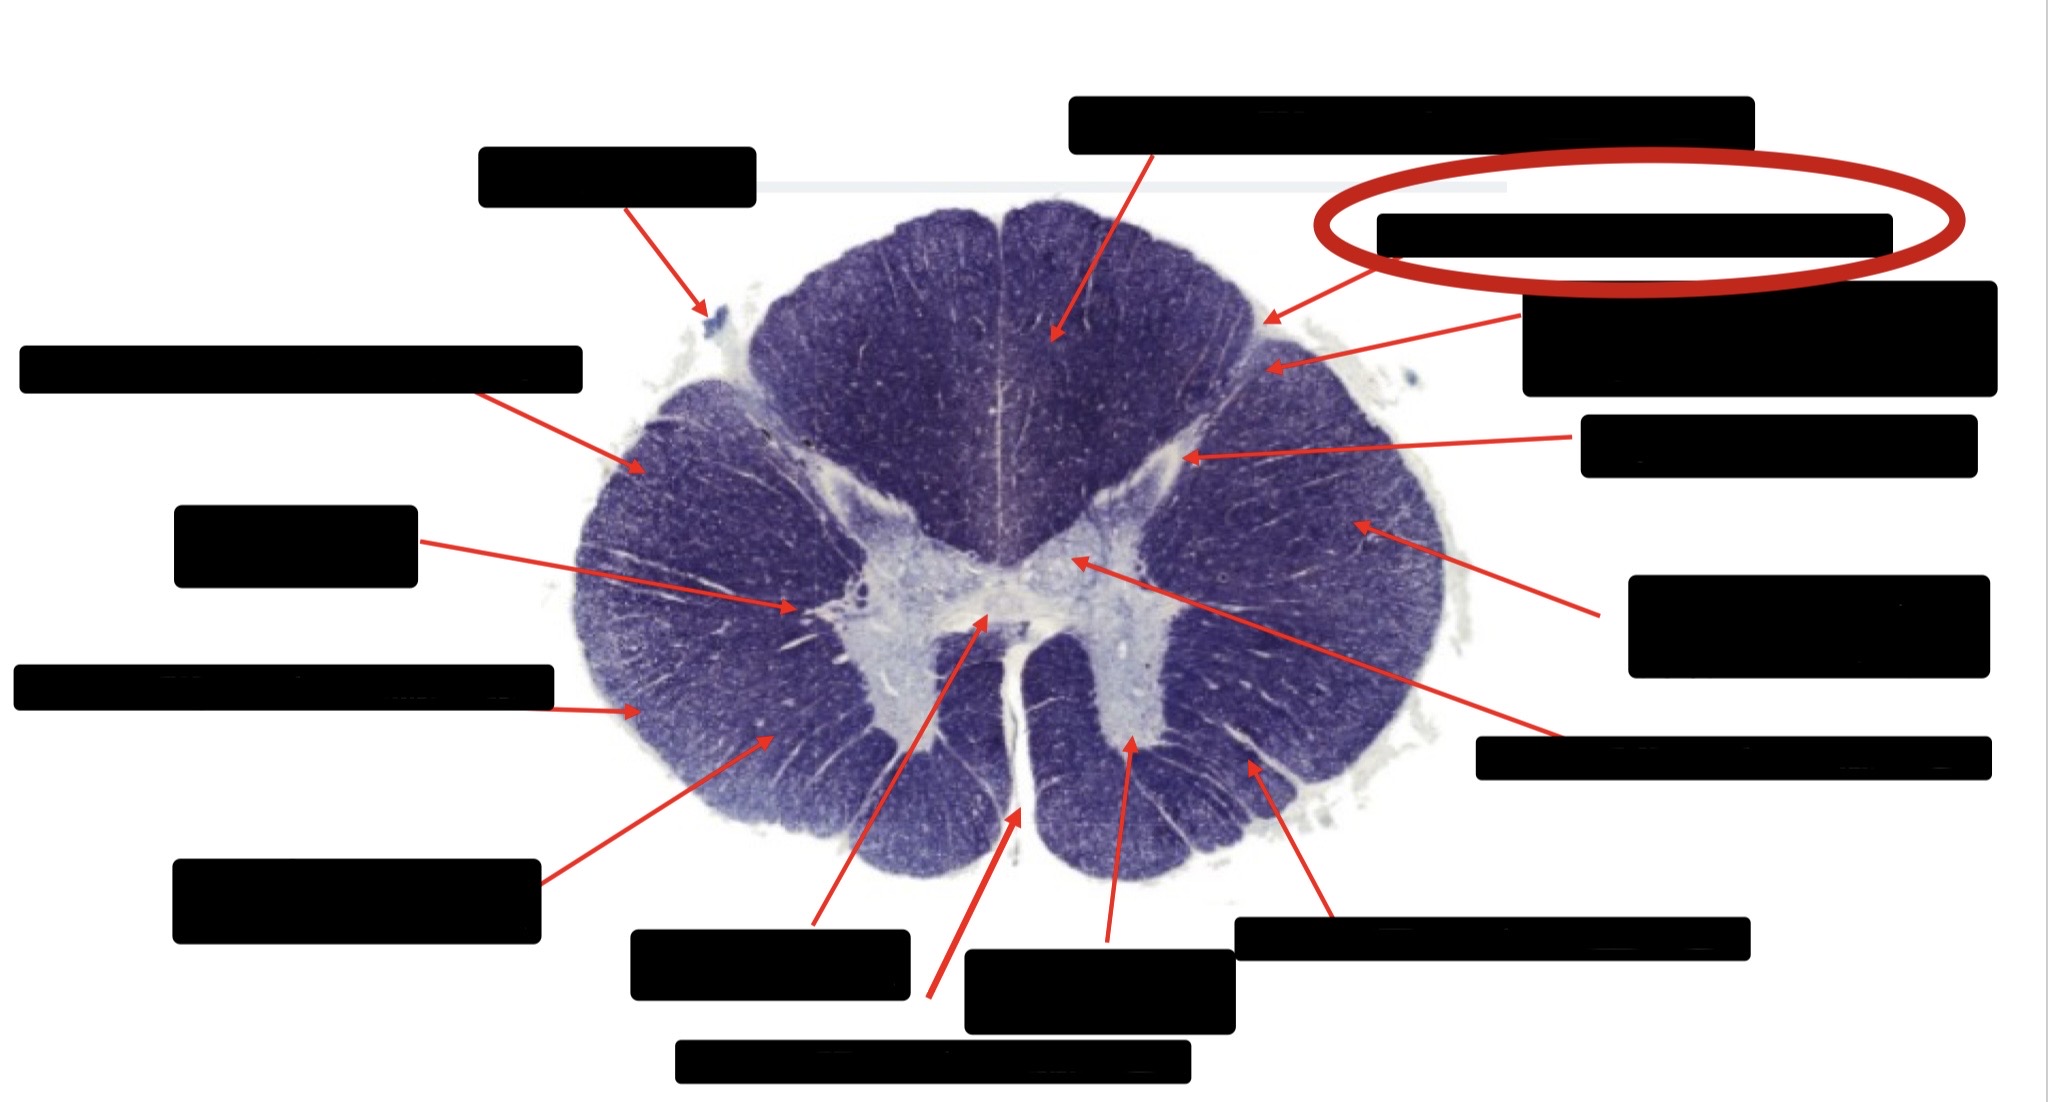

Spinothalmic Tract

Central Canal

Posterior Column (Fasciculus Gracilis)

Large Fiber Entry Zone

Lissaeur’s Tract & Small Fiber Entry Zone

Substantia Gelatinosa

Lateral Corticospinal Tract

Ventral Root Fibers

Anterior Horn Motor Neurons

Anterior Medial Fissure

Dorsal Rootlet

Posterior Spinocerebellar Tract

Anterior Spinocerebellar Tract

Posterior Column (Fasciculus Cuneatus)

Anterior Horn Motor Neurons (Distal Muscles)

Anterior Horn Motor Neurons (Proximal Muscles)

Anterior Corticospinal Tract